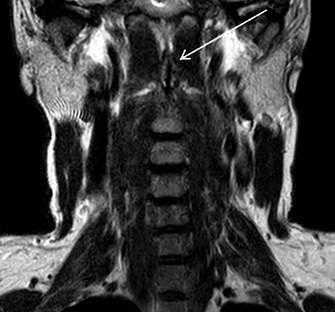

На мр-томограммах выявлялась расщелина (незаращение) передней дужки атланта, определялись особенности анатомического строения и особенности контуров передней дужки атланта в каждой из стандартных проекций (рис. 2).

Рис. 2. Коронарный и сагиттальный срезы Т2ВИ (стрелкой указаны поверхности расщепленной передней дужки)

Также обращали внимание на возможные изменения конфигурации строения зубовидного отростка осевого позвонка, связочного аппарата – толщину поперечной связки атланта, анатомическое строение составляющих атланто-затылочных суставов и дегенеративные изменения атланто-дентального сустава. Помимо выявления незаращения передней дужки атланта, определяли морфологические изменения, возникающие в процессе онтогенеза в атланто-дентальном суставе. Определяли влияние наличия расщепления передней дужки на ее анатомическую конфигурацию.